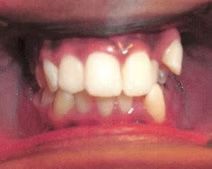

Emily

Emily didn't like how her top teeth were turned in and the lower teeth were crowded. Her bite was slightly off on both sides. Emily just needed upper and lower braces to correct her dental alignment and some rubber bands to correct the bite. She absolutely loves her teeth now!